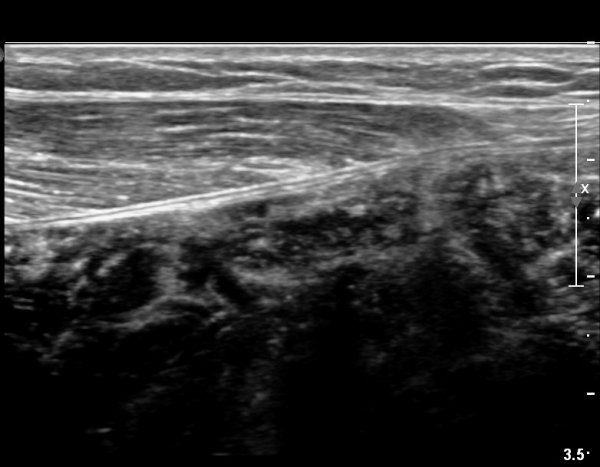

[¹ß¸ñ] simultaneosus tear of GCM and achiles tendon

pain on rt. leg( du: 1 day)

abrupt leg pain developed during foot volleyball

he walk with severe limping with no weight bearing on rt. leg. on examination, there is local tendernes at GCM and achiles tendon, severe pain with ankle dorsiflexion.

ÃÊÀ½ÆÄ °Ë»ç